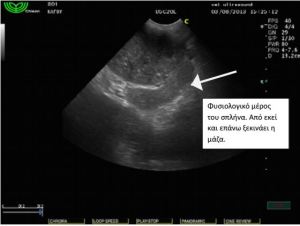

Στον υπέρηχο κοιλίας βρέθηκε μάζα σπηλαιώδης, η οποία

ξεκινούσε από τον σπλήνα και καταλάμβανε μέρος της πρόσθιας

κοιλίας καθώς και παρουσία ασκητικού υγρού. Το ήπαρ φαινόταν

φυσιολογικό χωρίς απώλεια της δομής και του σχήματός του.